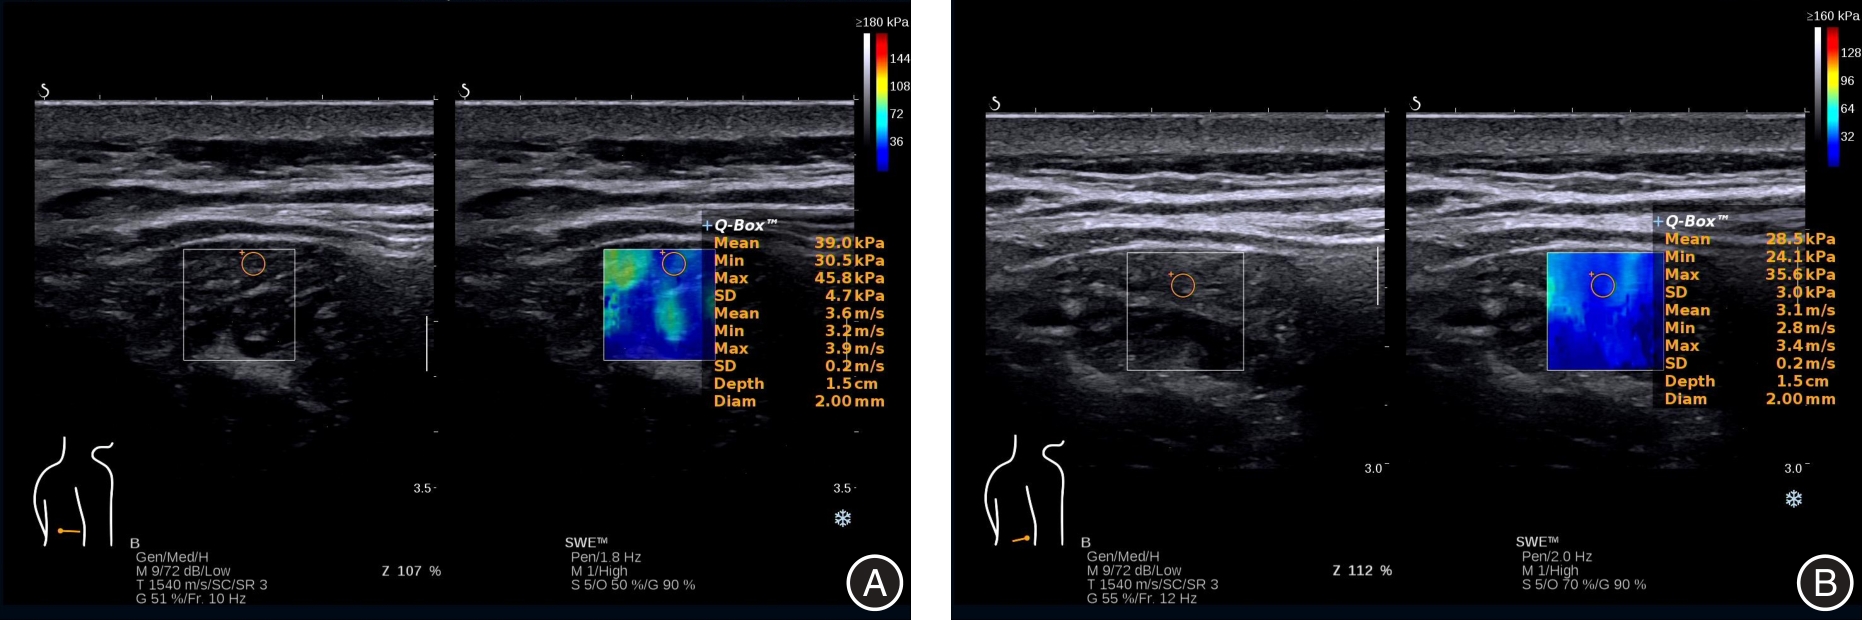

目的 分析四维牵引治疗老年退行性腰椎管狭窄症(DLSS)疗效、腰肌形态学及力学性能的效果。 方法 选择2022年1月至2024年2月广州中医药大学第二附属医院收治的老年DLSS患者按治疗方式分为观察组(肌肉锻炼+四维牵引,40例)和对照组(常规肌肉锻炼,40例)。对照组接受常规肌肉锻炼,观察组接受肌肉锻炼+四维牵引治疗,治疗4周。进行超声多模态检查,比较两组腰肌肌群形态学、力学性能、腰椎活动度、间歇性跛行距离、视觉模拟评分(VAS)、Oswestry功能障碍指数(ODI)。 结果 治疗后,观察组多裂肌厚度、多裂肌周长、多裂肌横截面积、压痛阈、腰椎活动度均大于对照组(P < 0.05),多裂肌剪切波速度(SWV)、多裂肌杨氏模量、肌张力、屈曲伸直比均小于对照组(P < 0.05),间歇性跛行距离长于对照组(P < 0.05)。治疗结束后及随访12个月期间,观察组VAS评分、ODI指数均低于对照组(P < 0.05)。 结论 四维牵引联合肌肉锻炼治疗能有效改善老年DLSS患者的临床症状、肌肉功能和力学性能。

Objective To evaluate the efficacy of four-dimensional traction in elderly patients with degenerative lumbar spinal stenosis (DLSS), focusing on changes in lumbar muscle morphology and mechanical properties. Methods Elderly patients with DLSS admitted to the Second Affiliated Hospital of Guangzhou University of Chinese Medicine from January 2022 to February 2024 were enrolled. Based on the treatment method, they were categorized into the study group (muscle exercise combined with four-dimensional traction, n = 40) and the control group (routine muscle exercise, n = 40). All participants underwent a 4-week treatment regimen and subsequently received multimodal ultrasound examinations. The morphology and mechanical properties of the lumbar muscle group, lumbar range of motion, walking distance in intermittent claudication, Visual Analogue Scale (VAS), and Oswestry Disability Index (ODI) scores were compared between the two groups. Results After treatment, the study group exhibited significantly greater improvements in multifidus muscle thickness, circumference, cross-sectional area, pressure pain threshold, and lumbar range of motion (P < 0.05). In contrast, the shear wave velocity (SWV), Young's modulus, muscle tension, and flexion-extension ratio of the multifidus muscle were significantly lower in the study group (P < 0.05). Additionally, the walking distance in intermittent claudication for the study group was markedly longer (P < 0.05). During the 12-month follow-up period after treatment, the VAS and ODI scores of the study group remained significantly lower (P < 0.05). Conclusion Four-dimensional traction in combination with muscle exercise can effectively alleviate clinical symptoms, enhance muscle function, and improve mechanical properties in elderly patients with DLSS.